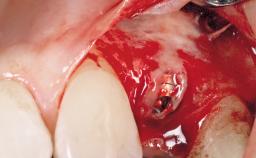

Bone Augmentation Horizontal|Simultaneous

Augmentation Materials Autogenous chips|Membrane

Placement Protocol Immediate implant placement

Socket Integrity Sufficient, with intact bone walls

Bone Volume Sufficient, with intact walls